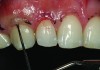

Before bonding, the enamel was etched with 37% phosphoric acid (ETCH-37™ 37% Phosphoric Acid Etchant, BISCO, Inc., www.bisco.com). A dentinal adhesive (ALL-BOND UNIVERSAL®, BISCO, Inc.) was placed, blown thin for 10 seconds with forceful compressed air, and then light-cured for 20 seconds (Figure 4). Using an injectable composite resin (G-ænial Universal Flo), a sequence of composite resin layering was performed to blend the composite resin to the existing tooth and create a natural polychromatic effect. To match the chromaticity along the gingival area, an opacious dentin shade, AO2, was bonded over the RMGI to mimic the lost dentin (Figure 5). Using a free-hand sculpt technique, universal shade A2 was injected over the opacious dentin composite resin with an emphasis on placing a convex anatomy to simulate natural dentition. Because of the chameleon effect and the depth of color of the body shade A2, no other shades were needed (Figure 6).